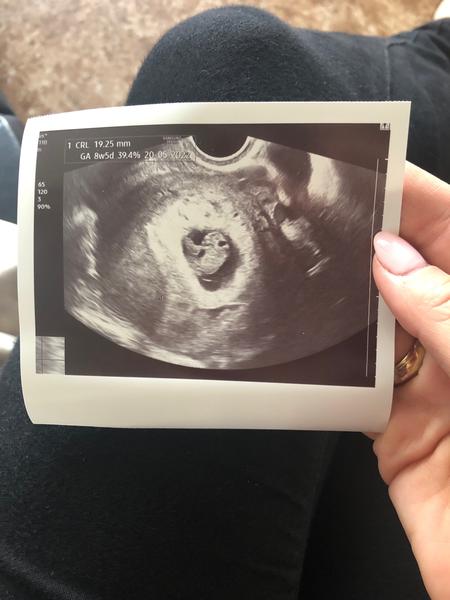

@veronika111111111 ahojky, tak miminko nakonec odpovídá a vše dohnalo, srdíčko bije a odpovídá 8+5 ❤️. Takže hlavu vzhůru, držím palce 🍀

No sycak by mi ji snad neudelal 😁, vyloženě jsem si o ní řekla a zaplatila za ní 100 Kč 😁...ale mám ji 💪.